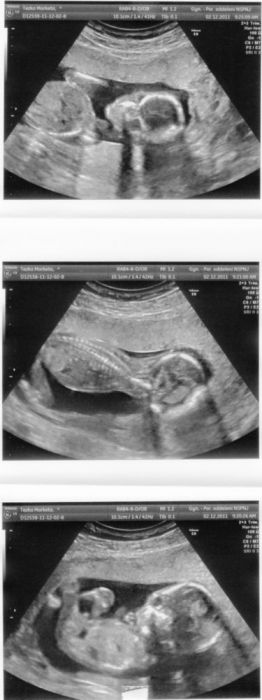

takže dovolte, abych vám představila našeho prďoška :-) na té druhé fotce ovšem vypadá jak UFOnek :-)

oprava, ufonek je na té trojfotce, hned ta první, ta poslední je pak zvětšená a to je ta druhá fotka a kdo najde pindíka????

No, to je už nádherné, obrovské miminko, Yashi! To je úžasné a dojemné! Pindíka vidím

[59518]Yashi máš krásné miminko pod srdíčkem, podle UZ se mu ve Tvém bříšku strašně moc líbí

podle toho jak si tam hoví

[59518] yashi, to je krásné. Jde nádherně vidět, že to je chlapeček. :-) To já mám s posledního UZ spíš fotku medvídka, kulatá hlavička, kulaté bříško a jako by měl jen takové kulaté pacinky, které mu trčí z bříška. :-)